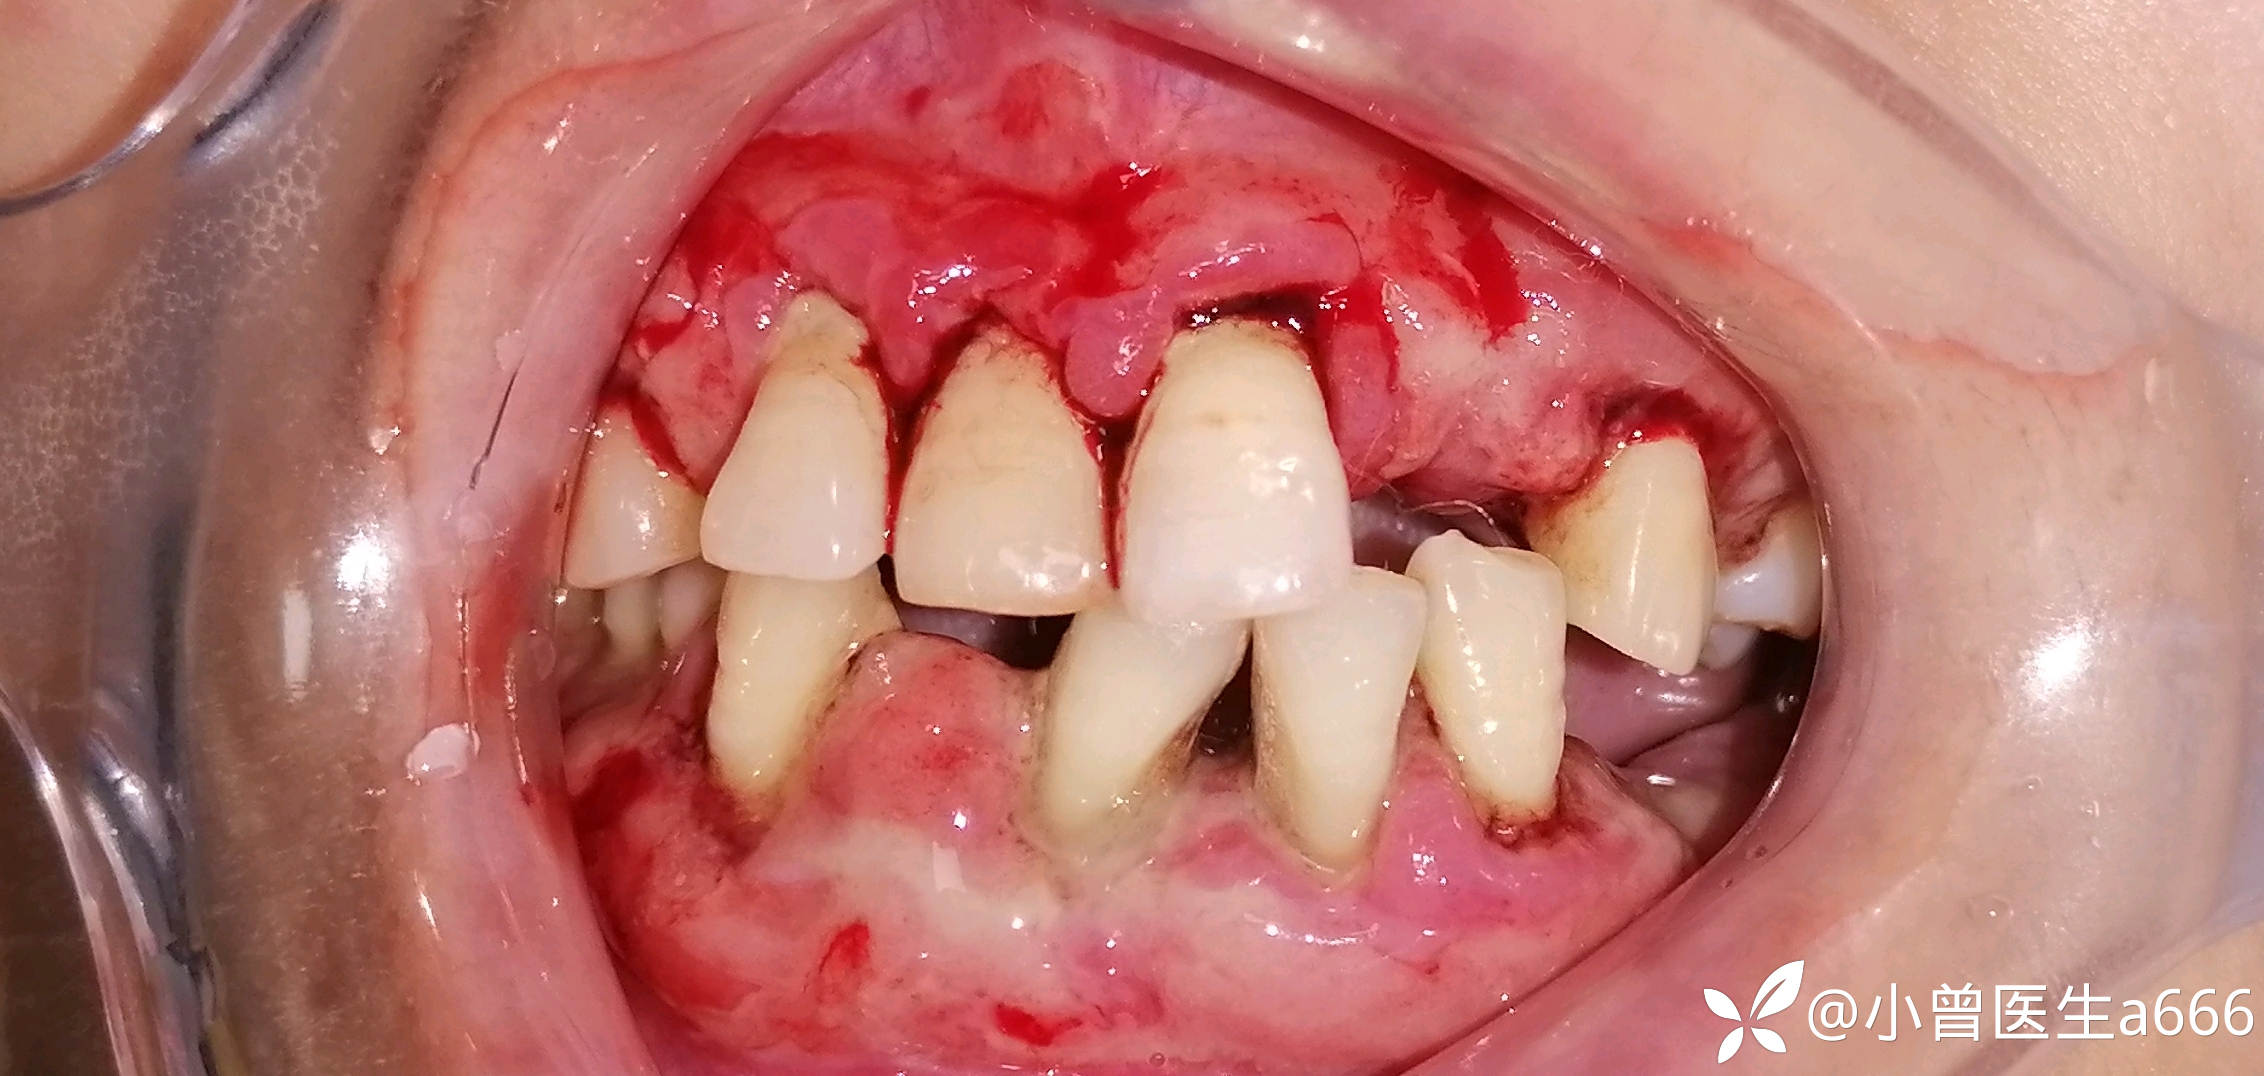

简要病史:患者自诉10年前发现刷牙出血情况,牙齿逐渐松动至脱落,只剩下口内这几颗牙了,剩下的牙都是松动三度的。4年前诊断出高血压,有服药史。

体格检查:全口牙龈红肿,探诊出血(+++),牙龈大面积溃疡溢脓,可探及深牙周袋,牙龈质软,牙龈退缩牙根暴露,见少量牙结石及软垢。牙龈牙齿检查未见疼痛不适。41缺失,41处牙龈肿胀增生至切1/3—1/2。视诊见下眼睑苍白无血色,皮肤暗黄,可见双臂皮肤斑点(患者自诉是过敏而致)

临床诊断:系统性疾病型牙周炎?